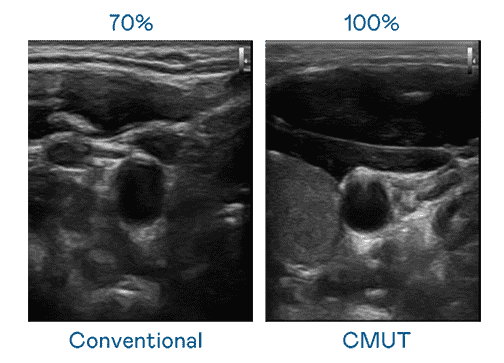

CMUT 技术是一种用电容式微机电元件来产生超音波讯号的技术。。与传统 PZT 压电式技术相比,,,,CMUT 频宽增加 30%,,,更宽频的超音波讯号让影像解析度大幅提升,,是实现高影像品质医疗超音波扫描、、促进精准医疗发展的关键技术。。。

大频宽带来超清晰影像

超音波影像的解析度高低,,首先取决于探头能发出的讯号频宽。。。。汇旺支付 CMUT 可提供高清晰的超音波讯号,,,提供高频宽、、、、高灵敏度、、影像纹理细节更高的超音波影像,,,协助医护人员缩短影像判读时间及利用精准的医疗影像进行诊断。。。